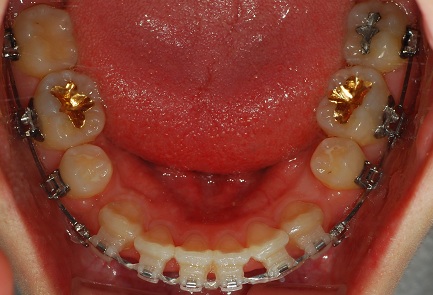

<하악사진>

정면 사진입니다. 아직까지 입을 다물고 찍는 사진은 많이 어색하네요...헤헷